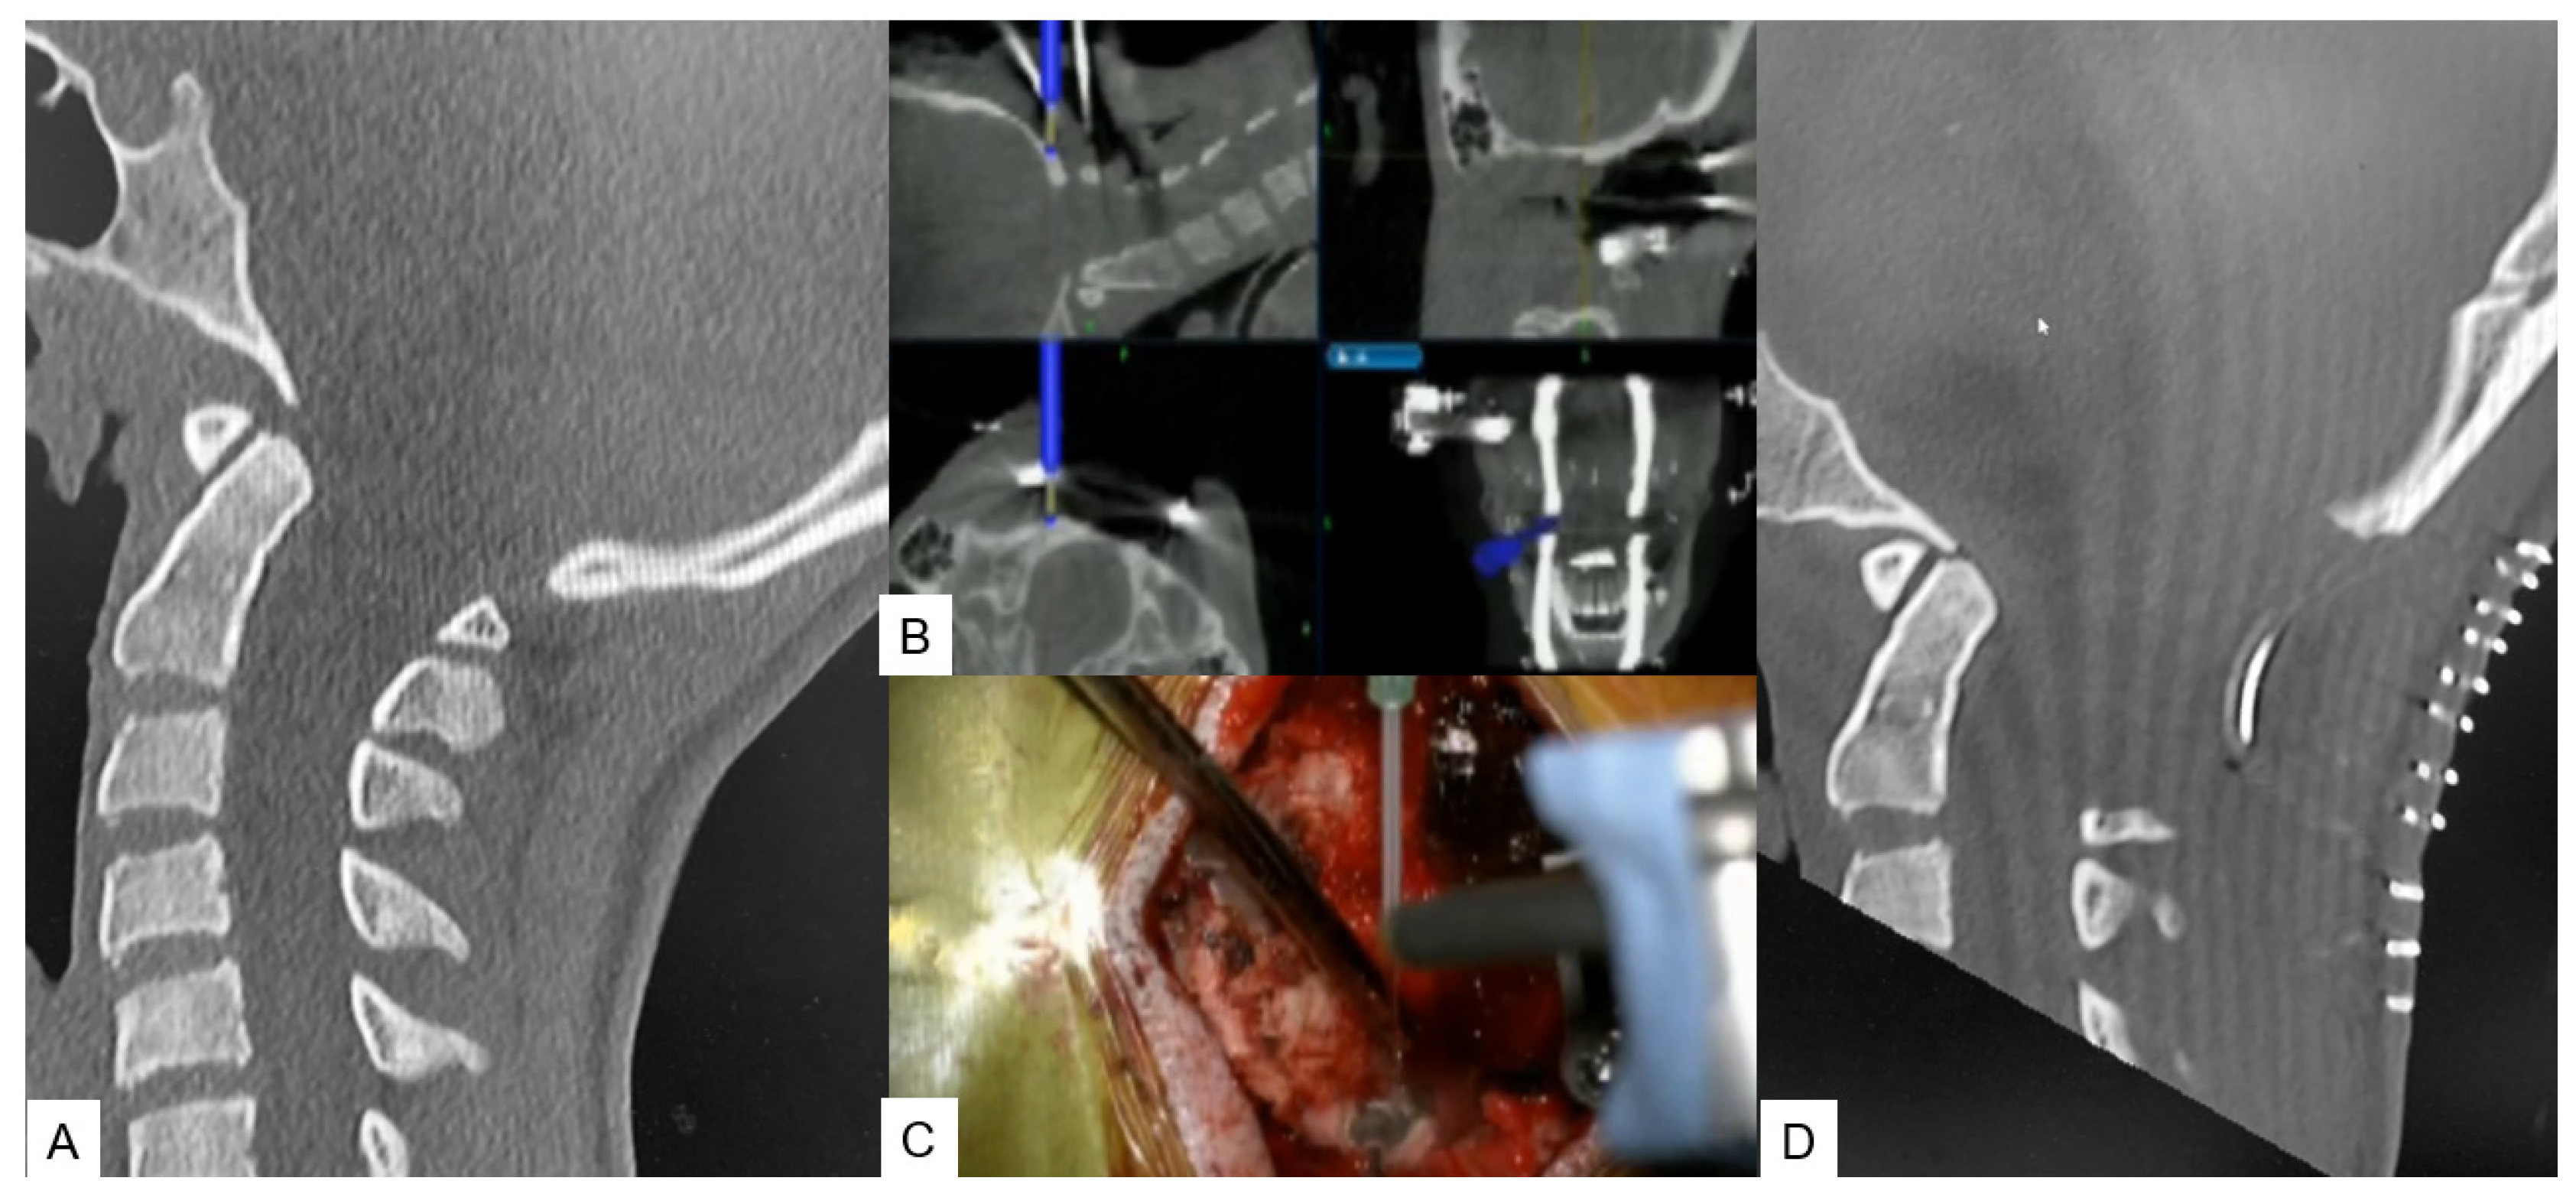

OPLL Resection

- Tanaka, M.; Suthar, H.; Fujiwara, Y.; Oda, Y.; Uotani, K.; Arataki, S.; Yamauchi, T.; Misawa, H. Intraoperative O-arm navigation guided anterior cervical surgery; A technical note and case series. Interdiscip. Neurosurg. 2021, 26, 101288. [Google Scholar] [CrossRef]